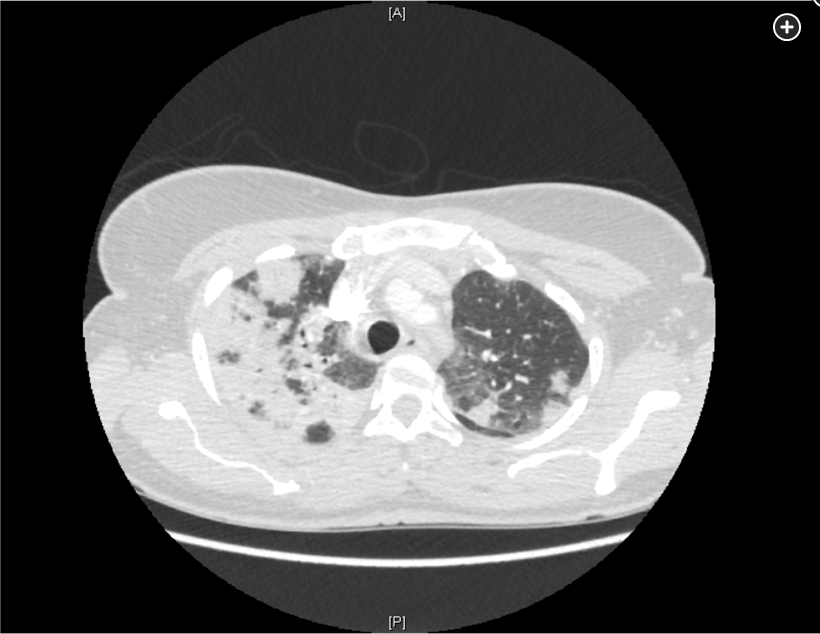

Diagnosis of invasive aspergillosis would ideally be based on tissue biopsy showing invasion with organisms showing the typical acutely branching hyphal morphology consistent with Aspergillus species and positive culture (see Figure 4). Biopsy is often not possible in patients who are critically ill, and alternative diagnostic methods may be employed. Testing for fungal antigens such as galactomannan or β-D-glucan can be performed on serum and/or BAL fluid, and a serum polymerase chain reaction test is available from reference laboratories. Serum tests for galactomannan and β-D-glucan were strongly positive in this patient. Radiologic findings can also strongly suggest a diagnosis of invasive fungal disease. Often, there are dense nodular infiltrates (as seen on the CT scan performed on this patient), and there may be halo or reverse halo signs. The halo sign consists of ground glass density surrounding a dense nodule, as shown in Figure 5. It is thought to correlate with areas of hemorrhage surrounding denser areas of active infection, and pathologically invasive aspergillosis is characterized by areas of hemorrhage and infarction. The reverse halo sign, which was present on the CT scan of this patient (see Figure 6, arrow), is described as a rim of high attenuation surrounding an area that likely represents infarction.

Symptoms of IPA are nonspecific and usually mimic bronchopneumonia: fever unresponsive to antibiotics, cough, sputum production, and dyspnea. Patients may also present with pleuritic chest pain (due to vascular invasion leading to thromboses that cause small pulmonary infarcts) and hemoptysis, which is usually mild. IPA is one of the most common causes of hemoptysis in neutropenic patients. Chest x-ray may not detect early-stage disease (ie, small nodules). Chest computed tomography (CT) scan shows single or multiple nodules with or without cavitations and “halo sign” (nodules surrounded by ground-glass infiltrates). Diagnosis is suggested by culture and histology.

Clinicians have long been familiar with risk factors for pulmonary invasive aspergillosis, including prolonged neutropenia, bone marrow transplantation, and solid organ transplantation; however, there has been increasing recognition of this typically opportunistic infection in patients with prolonged ICU stays, including protracted periods of mechanical ventilation for viral pneumonia including infection by influenza and SARS-CoV-2, as in the patient presented here. This latter phenomenon has been termed covid-associated pulmonary aspergillosis (CAPA). In the context of the ICU, invasive pulmonary aspergillosis does not arise with radiologic evolution of nodular and necrotic change superimposed upon more normal lung fields but rather is often obscured by the cause of respiratory failure prompting initial ICU admission. Hence, an appropriate index of suspicion of Aspergillus infection must be present when evaluating patients who are critically ill with evidence of late (>10-14 days) complicating ICU infection. Diagnosis requires identification of the organism in tissue and/or body fluids and can also be supported by the serologic identification of components of the fungal cell wall, including galactomannan and 1,3-ß-D-glucan.